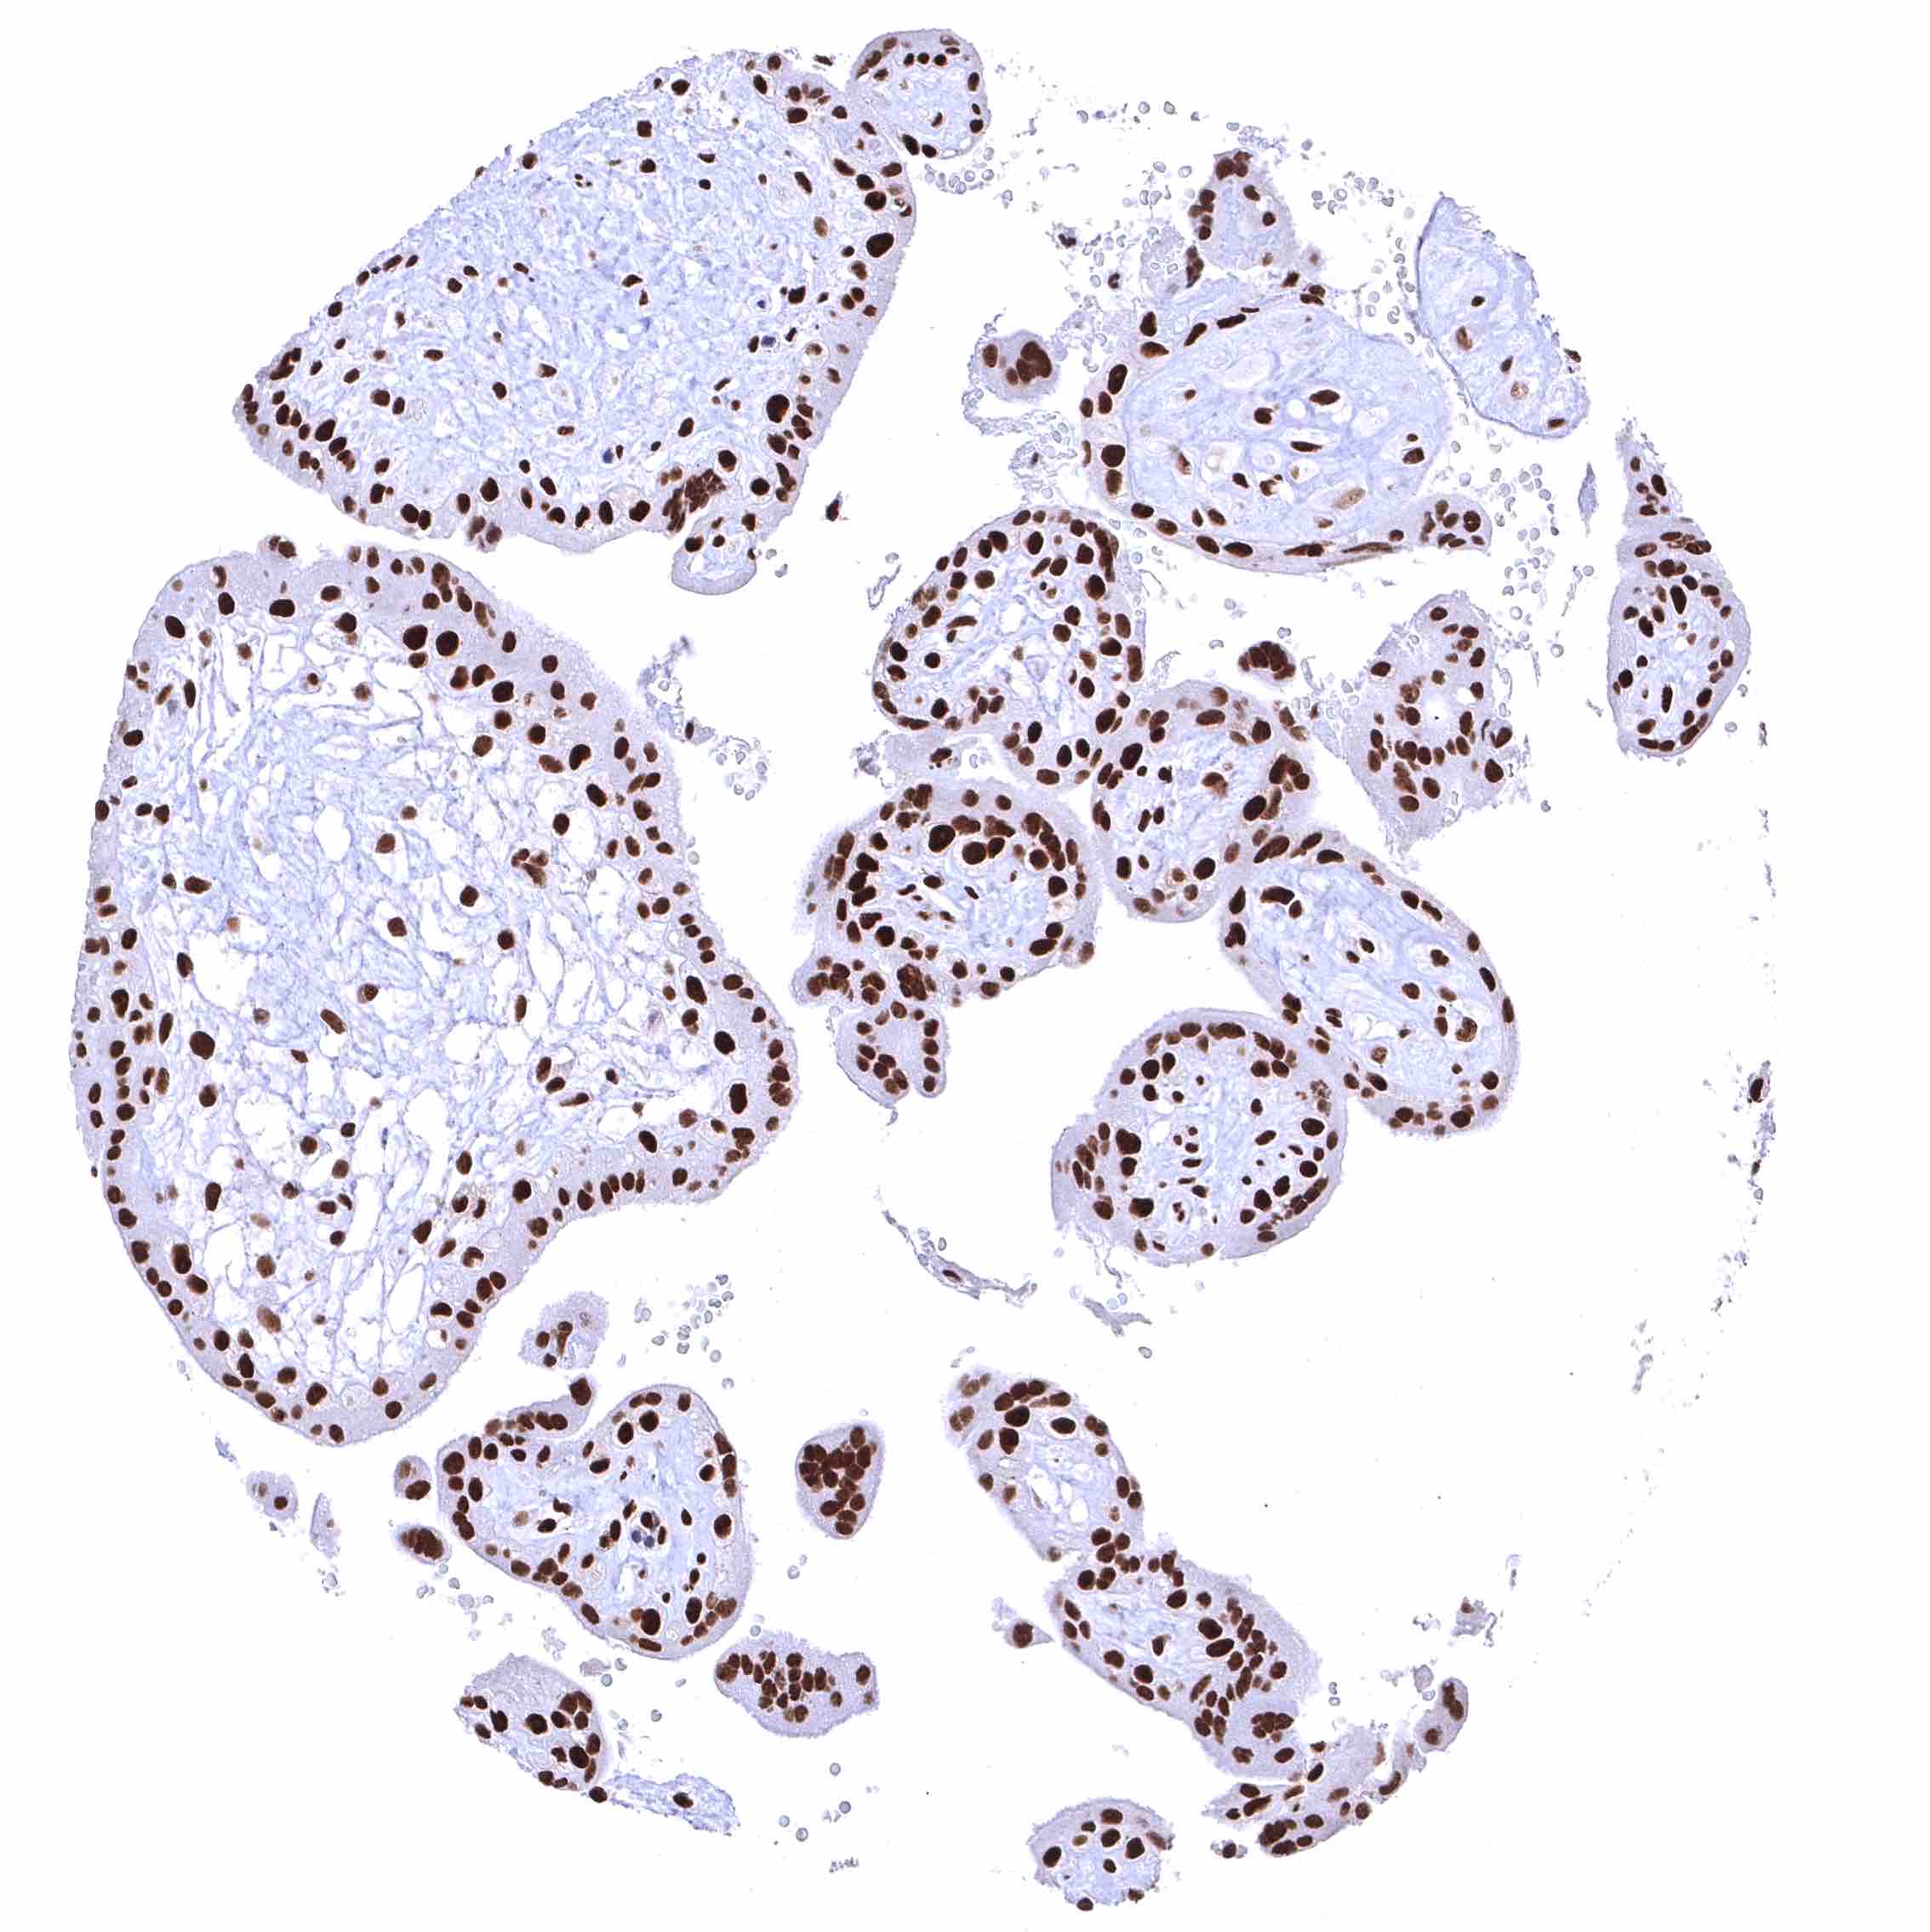

Placenta, early – Nuclear BRD4 staining is particularly strong in all trophoblast cells.